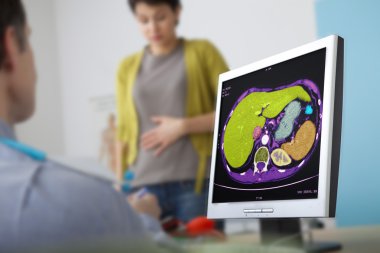

Doktor gösteren bebek ultrason görüntüsünün bilgisayara hamile kadına

tabloResimBilgisayarArkaplanKadıninsanlarKadınlarSağlıkçocukİlaçdikkatteknolojiKavramerkenDoktorHastaneekranmonitörHastaziyaretsahneKarnıGöbekGösterGelecekBebeğimanneüstdoğumgösteriliyorinceleyinDanışmaklinikFetüsyeni doğanhamileSağlıkçıgebelikEbeveynlikAnnelikprematüreultrasonultrasonikJinekologJinekolojiEchographyechoscopyBenzer İçerikler